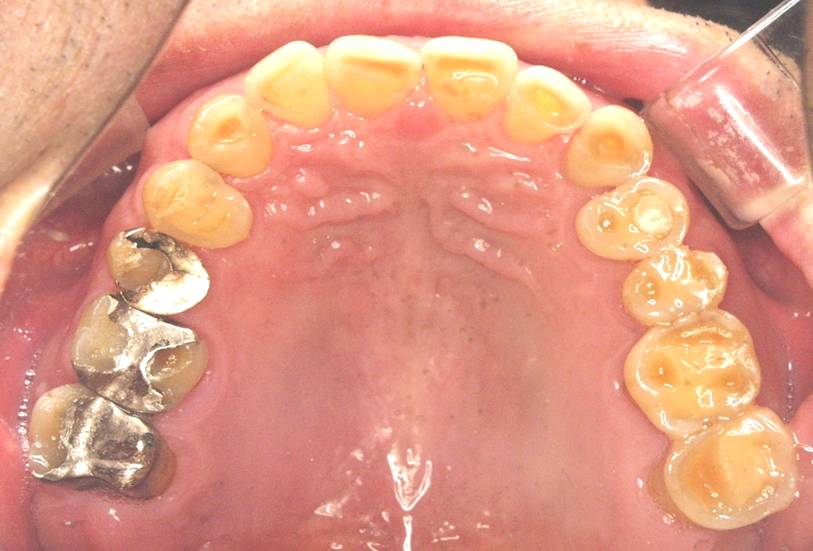

この写真は歯は全部残っていて抜いたことがないという方のお口の中の写真です。

硬いものをよく噛んでいました。

確かに歯の本数は残っています。

しかし、歯の頭がほとんどすり減って平になってしまっています。

しかし、長年ずっと使い続け硬いものを噛み続けて負荷がかかった歯は

このように歯の頭がすり減って平になってしまっています。

特に奥歯はかなりすり減ってしまっており、歯の中の神経が今にも露出しそうなほどになってしまっています。